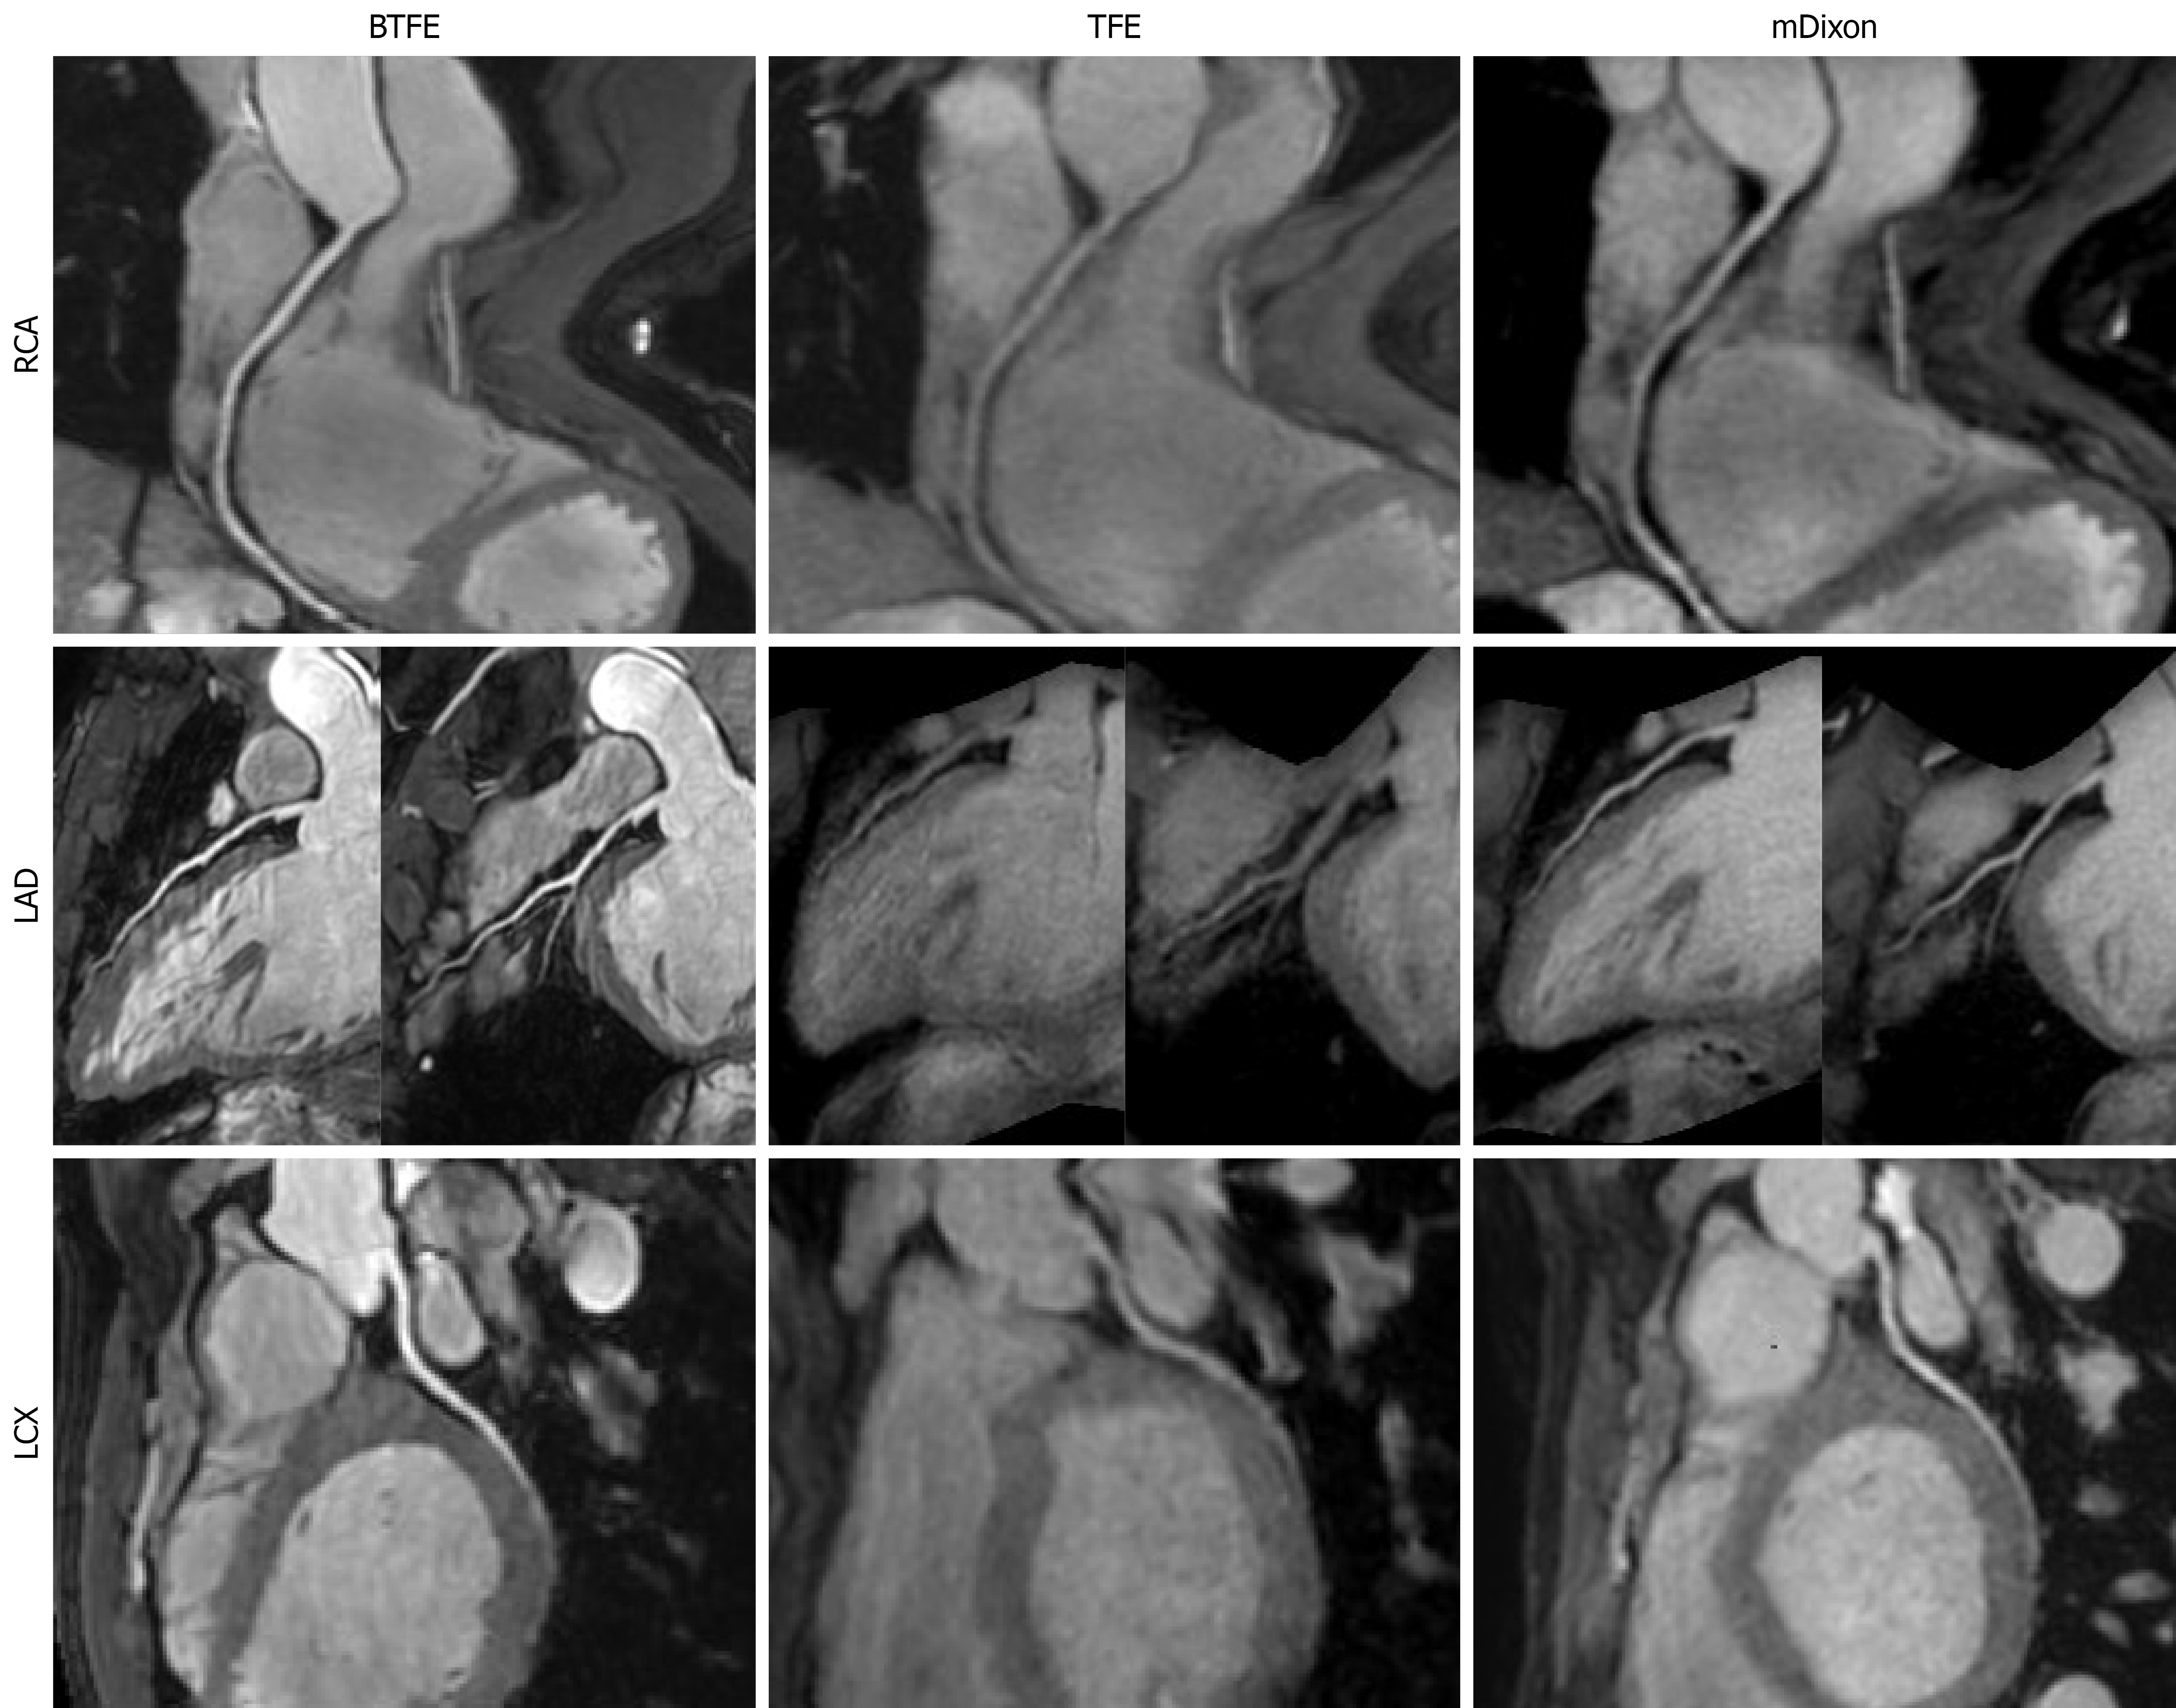

Figure 2 Non-contrast coronary magnetic resonance angiography images show the three major coronary arteries across the balanced turbo field echo, turbo field echo, and modified Dixon sequences.

The balanced turbo field echo (BTFE) sequence demonstrated superior image quality for all three arteries. In the right coronary artery, subjective image quality scores were 4 for BTFE, 2 for turbo field echo (TFE), and 3 for modified Dixon. The measured length of the left anterior descending artery was greater on BTFE images than on those acquired with TFE and modified Dixon. The lower contrast-to-noise ratio of the left circumflex artery on TFE likely explains its reduced measured length on that sequence. BTFE: Balanced turbo field echo; TFE: Turbo field echo; mDixon: Modified Dixon; LAD: Left anterior descending artery; LCX: Left circumflex artery; RCA: Right coronary artery.